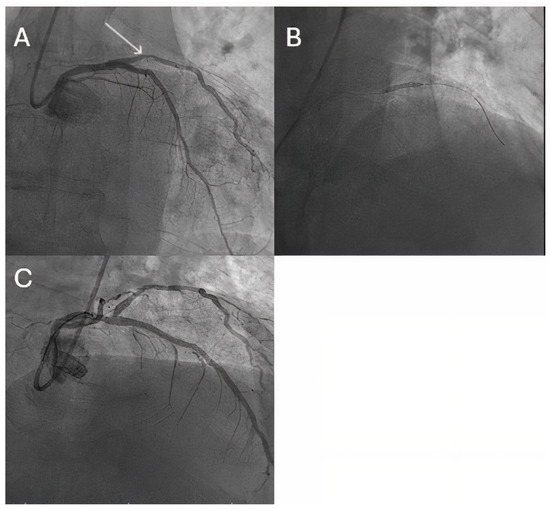

- Lazar, F.L.; Prvulović, Đ.; Onea, H.L.; Cortese, B. The role of drug-coated balloons for coronary bifurcation management: Results from the prospective EASTBOURNE-BIF study. Minerva Cardiol. Angiol. 2024, 72, 346–354. [Google Scholar] [CrossRef]

| Ke D et al. [74] | bifurcation lesions | lower LLL vs. DES (main-vessel: 0.05 ± 0.24 mm vs. 0.25 ± 0.35 mm, p = 0.013; side-branch: –0.02 ± 0.19 mm vs. 0.11 ± 0.15 mm, p = 0.005) |